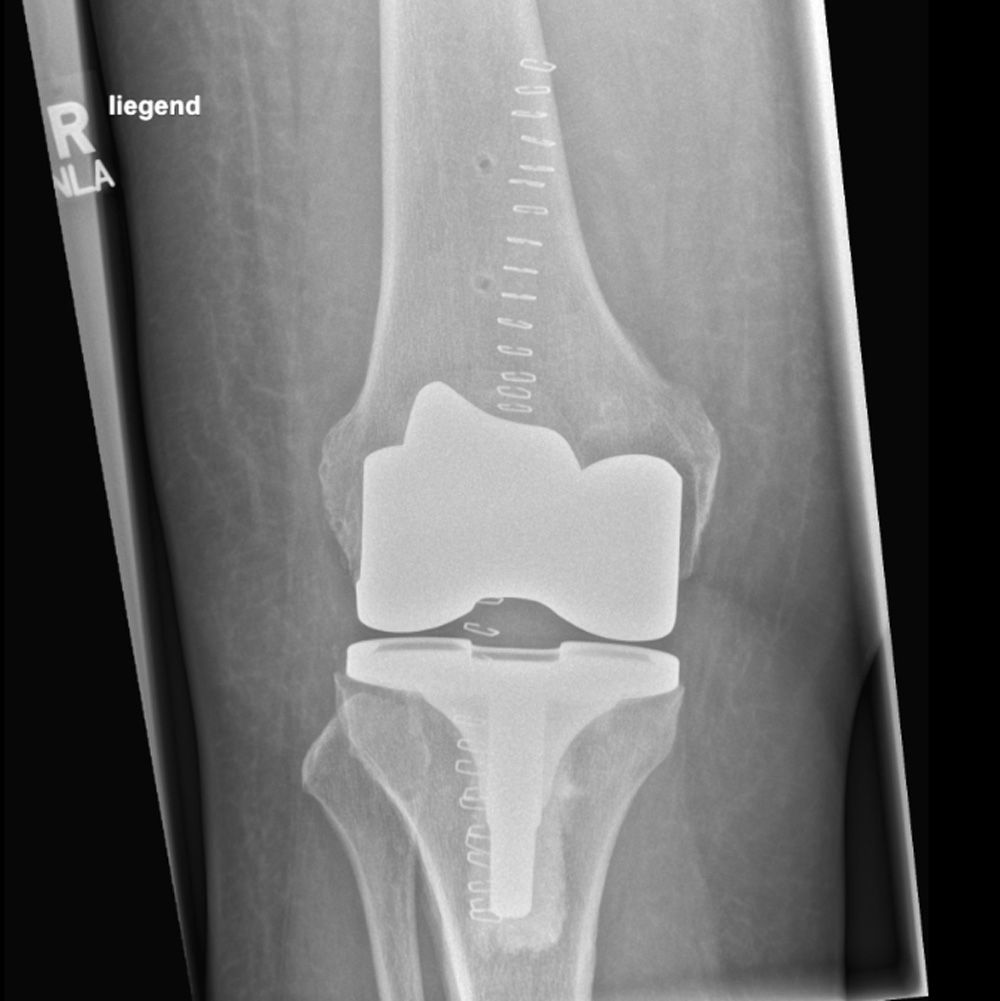

Röntgenbild einer Knievollprothese.